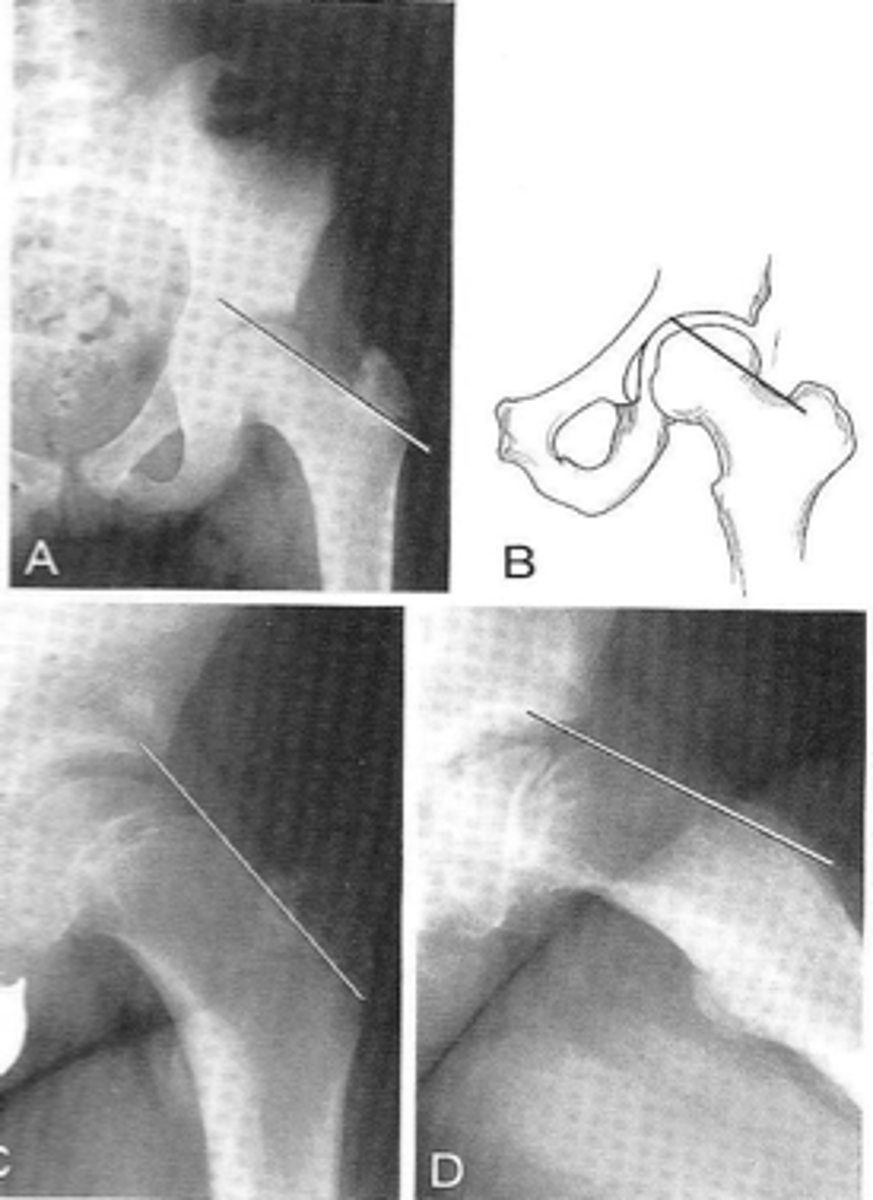

AP hip

View on left?

<p>View on left?</p>

Frog-leg hip

View on right?

<p>View on right?</p>